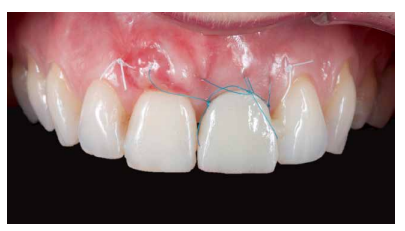

Los beneficios de la carga inmediata incluyen una reducción notable de las intervenciones quirúrgicas, una menor dilatación temporal del tratamiento e incluso un mejor bienestar psicológico y social para el paciente. En casos con importante compromiso estético, la carga inmediata o la provisionalización inmediata, añadida a la colocación inmediata postextracción del IOI permiten minimizar las alteraciones derivadas de la pérdida dental, manteniendo el perfil de emergencia, contorno de tejidos blandos y las papilas gingivales5-7.

Así mismo, se han establecido diferentes protocolos para el manejo del sector estético anterosuperior, que se suman al acto de la colocación inmediata del implante y la corona provisional, donde se incluyen la colocación de un material no reabsorbible entre el IOI y la cortical vestibular para minimizar el posible colapso, así como el manejo de los tejidos blandos periimplantarios8-11.